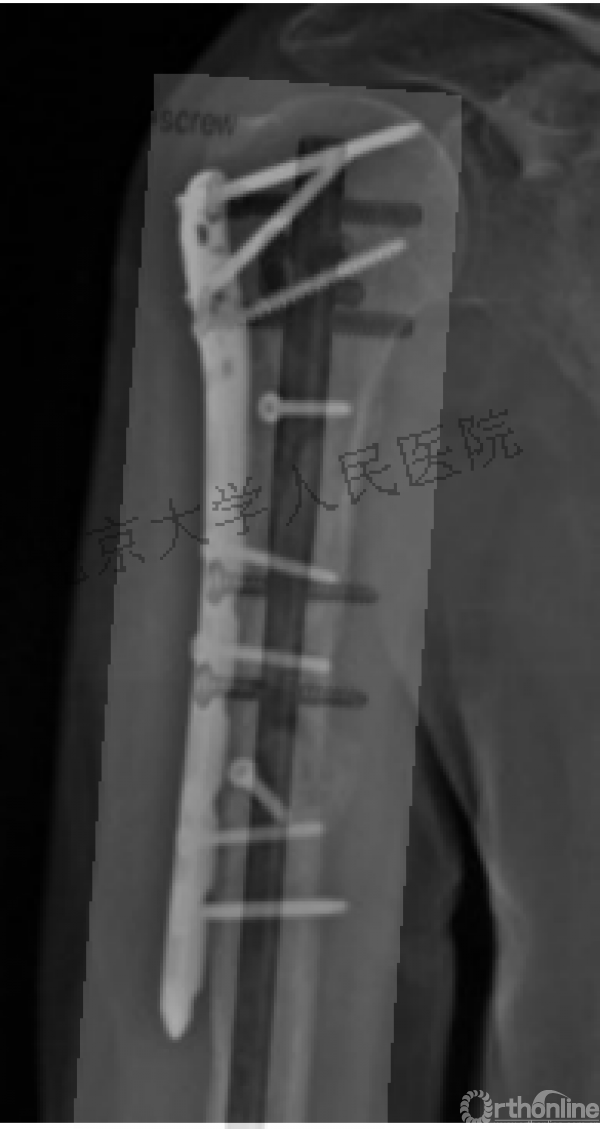

术中片